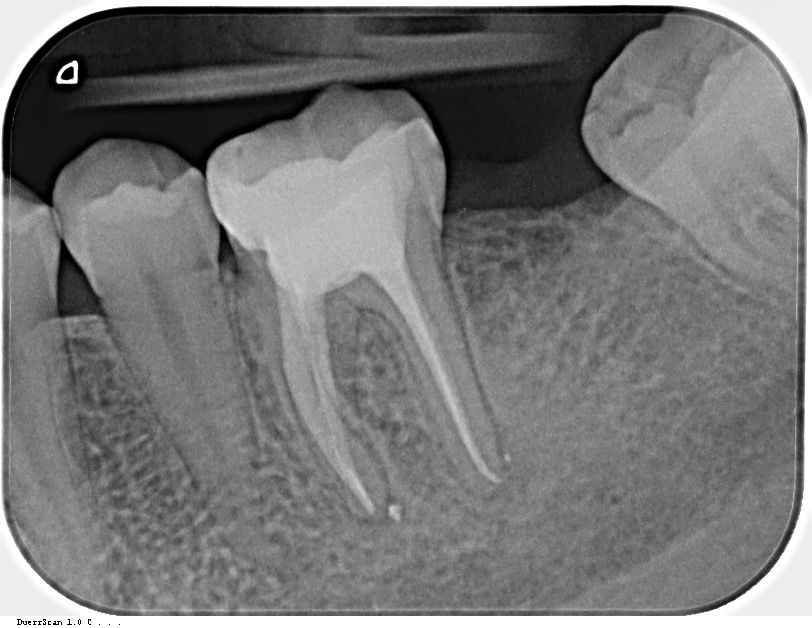

Zhojenie nálezu po 5 mesiacoch. MDDr. Gaľa